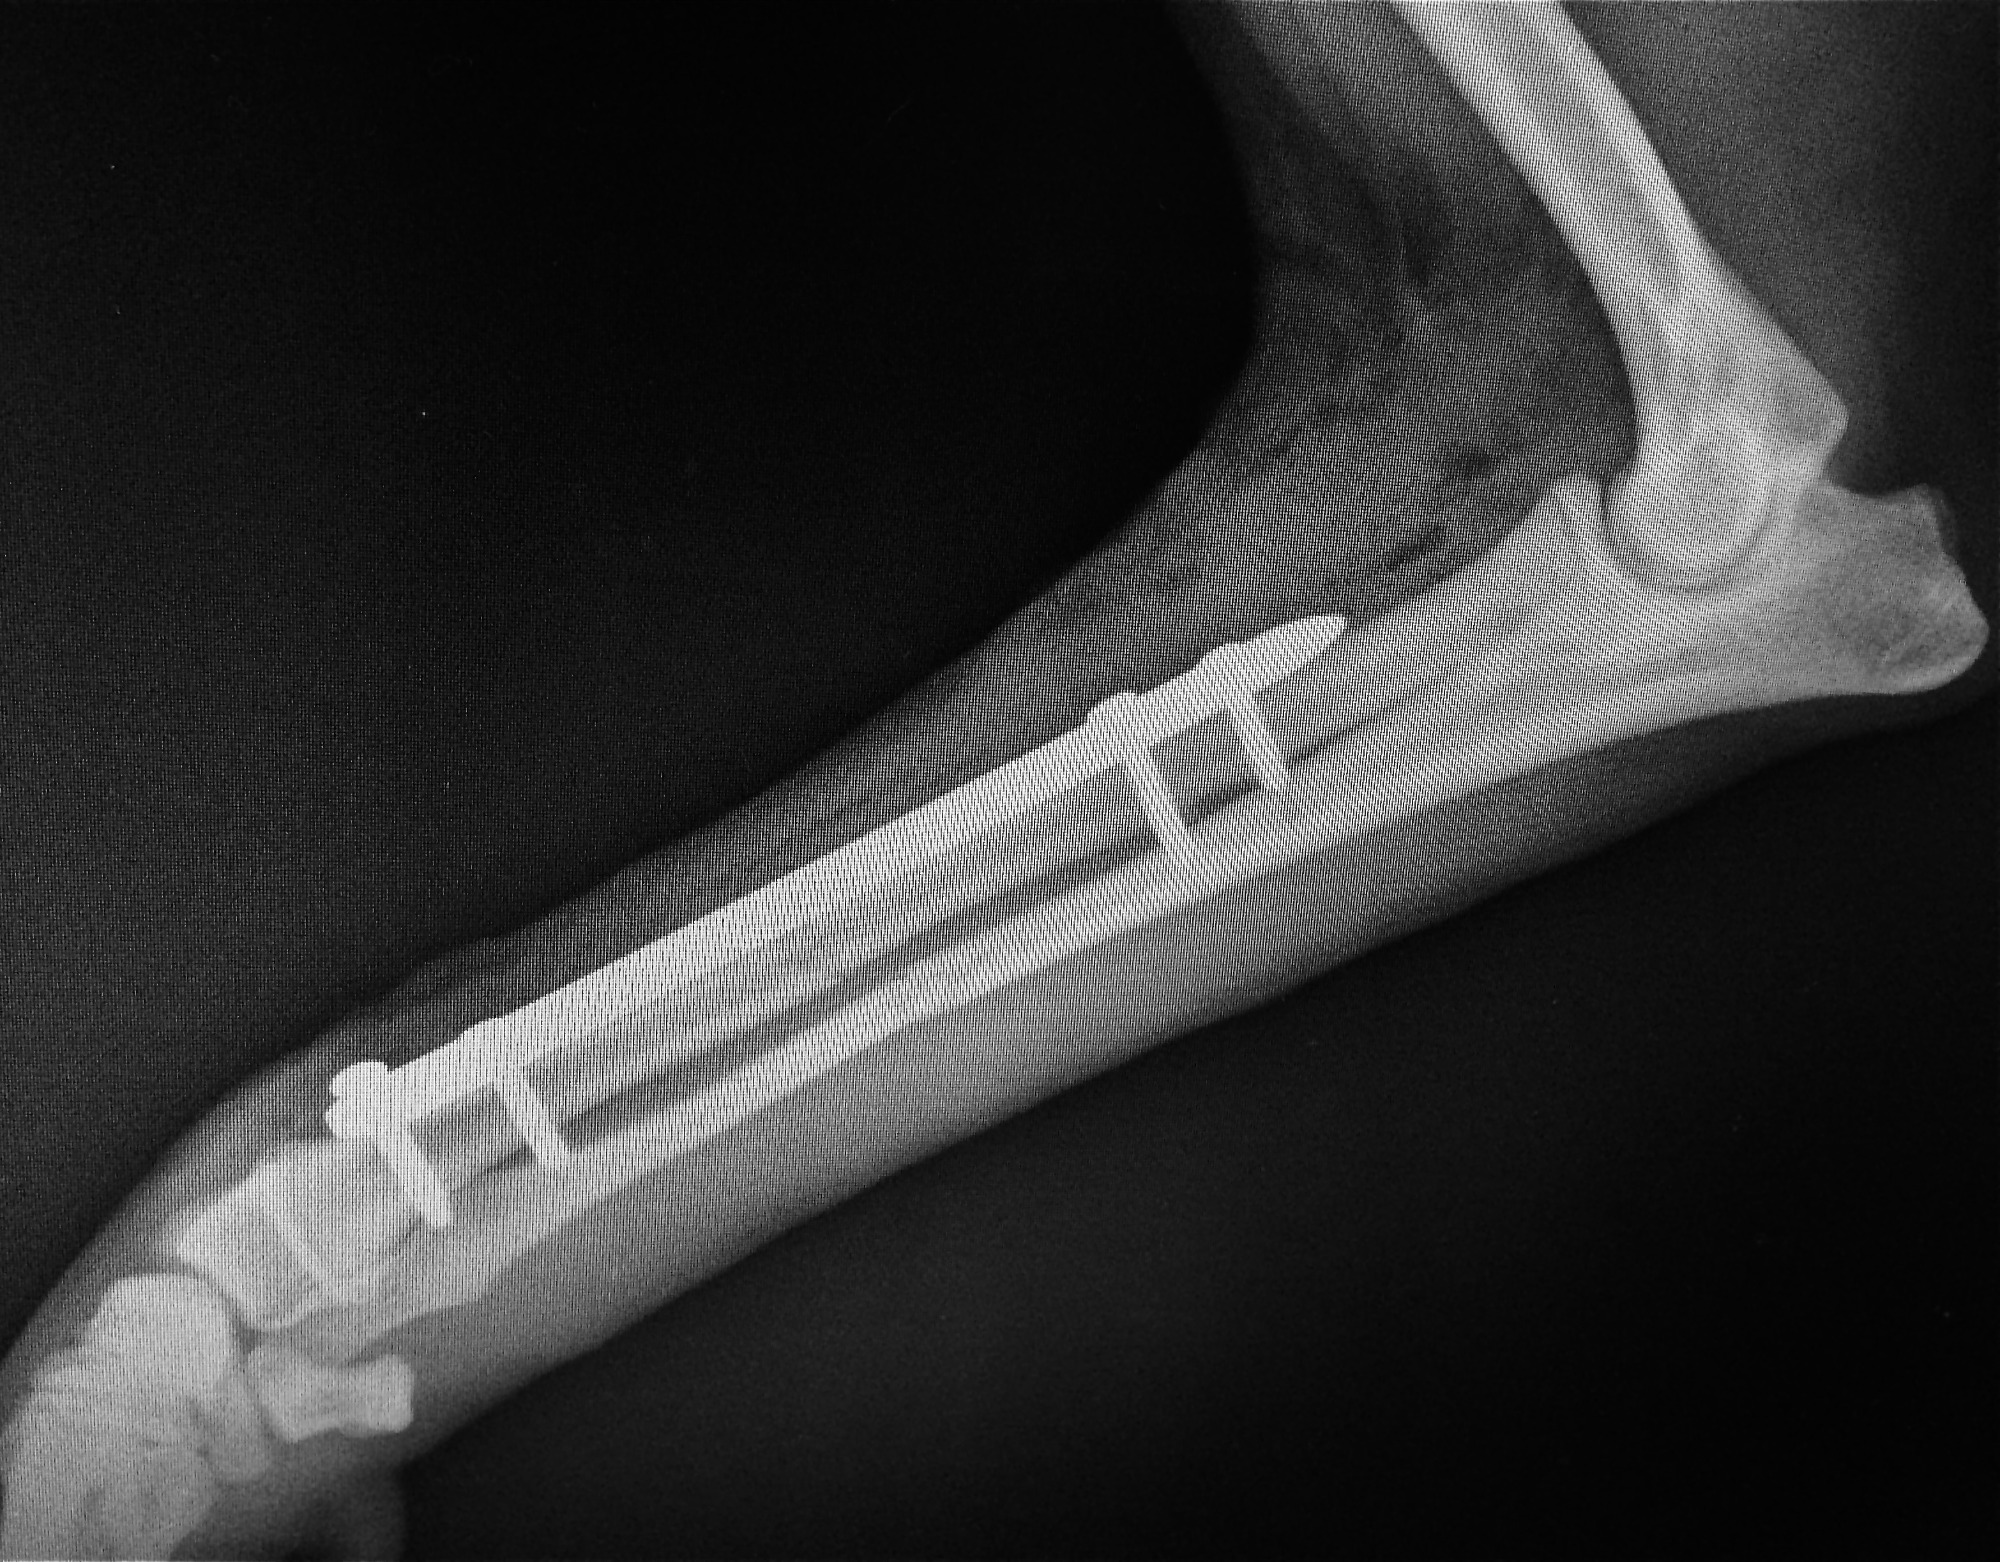

Frakturversorgung (Knochenbrüche)

Behandlung von Frakturen bei Hunden und Katzen mittels moderner Verfahren.

Ziel ist eine stabile Fixation, eine schnelle Heilung und die möglichst frühzeitige Wiederherstellung der Belastbarkeit.

Frakturversorgung mit Arthrex Implantate

Für die Behandlung von Knochenbrüchen verwenden wir moderne Implantate von höchster Qualität. Sie bieten eine sehr gute Stabilität und unterstützen eine sichere Heilung. Je nach Art der Fraktur kommen Implantate aus Titan oder hochwertigem chirurgischem Edelstahl zum Einsatz. Die Implantate sind in passenden Größen verfügbar und genau auf den Knochen und die Anatomie Ihres Tieres abgestimmt.